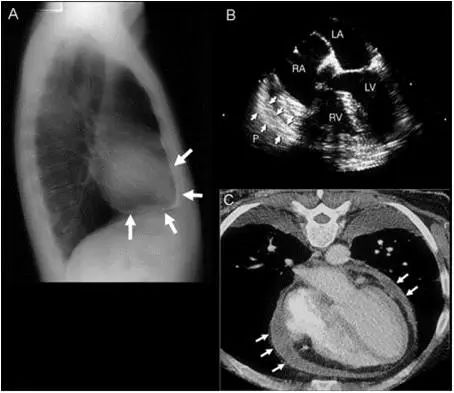

缩窄性心包炎影像学:A:X线; B :TEE;C:CT

缩窄性心包炎二尖瓣血流频谱:吸气时E峰值速度较呼气时减低>25%

A图:同步记录左室、右室压力,LV/RV舒张压力曲线呈平方根改变,与限制型心肌病 相同。

B图:同步记录左室及右房压力,LVEDP = RAP,与限制型心肌病不同。